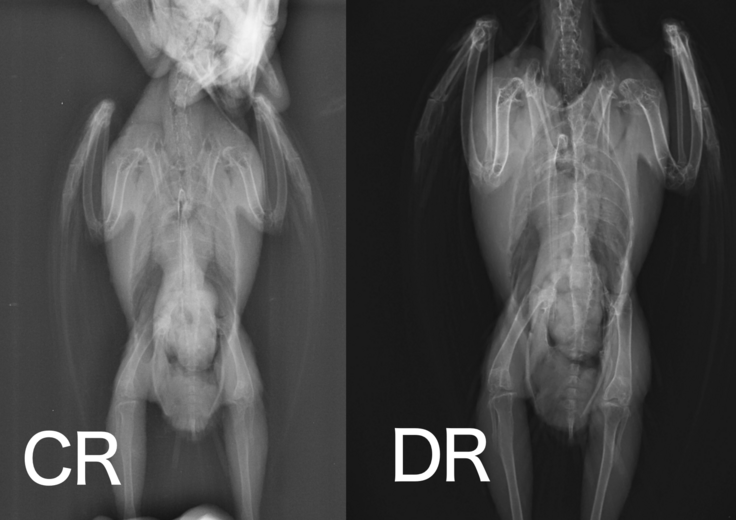

最近では撮影をし、機械に通すと自動で現像してくれてデータで画像を確認できます。(CR)

さらに新しいものだと、撮影してすぐに現像され画像が表示される仕組みになっております。(DR)

画像の鮮明度も上がって撮影時間も短縮できる時代になりました。

↑同じ鳥さんでもCRとDRでは見え方が変わってきます↑